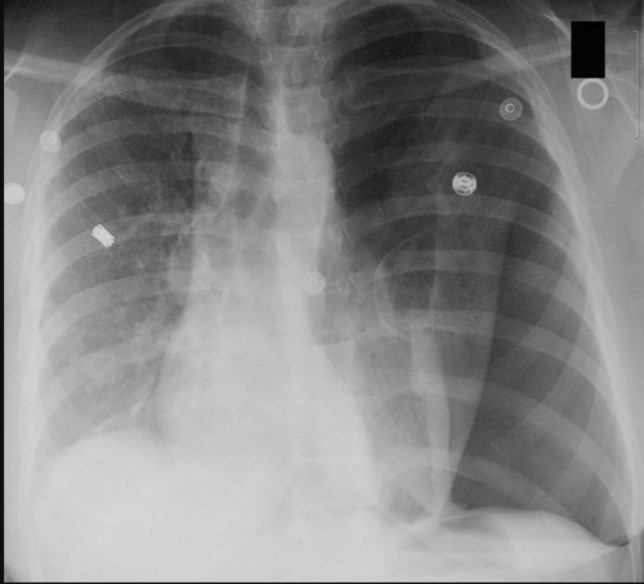

Image shows a left sided tension pneumothorax